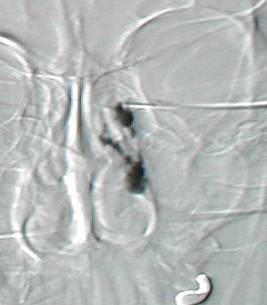

Right DCG showing lacrimal sac filling without drainage into the nasal cavity. In the last frame, dye shows up in the lower lid margin from regurgitation.